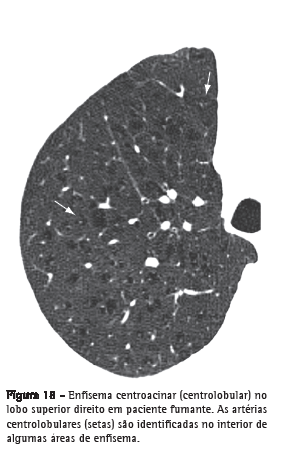

Enfisema centroacinarDestruição das paredes dos alvéolos centroacinares, associada ao aumento dos bronquíolos respiratórios e dos alvéolos que se originam nesses bronquíolos. É a forma mais comum de enfisema em fumantes de cigarro. Os achados tomográficos são de áreas centrolobulares de diminuição da atenuação, usualmente sem paredes visíveis, com distribuição não uniforme, predominantemente localizadas nas regiões pulmonares superiores (Figura 18).(37,38) As artérias centrolobulares podem frequentemente ser identificadas no interior das áreas hipodensas. O termo centrolobular é comumente utilizado como sinônimo na TC.